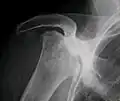

X-ray images of avascular necrosis in the early stages usually appear normal. In later stages it appears relatively more radio-opaque due to the nearby living bone becoming resorbed secondary to reactive hyperemia.[2] The necrotic bone itself does not show increased radiographic opacity, as dead bone cannot undergo bone resorption which is carried out by living osteoclasts.[2] Late radiographic signs also include a radiolucency area following the collapse of subchondral bone (crescent sign) and ringed regions of radiodensity resulting from saponification and calcification of marrow fat following medullary infarcts.

Radiography of total avascular necrosis of right humeral head. Woman of 81 years with diabetes of long evolution. -